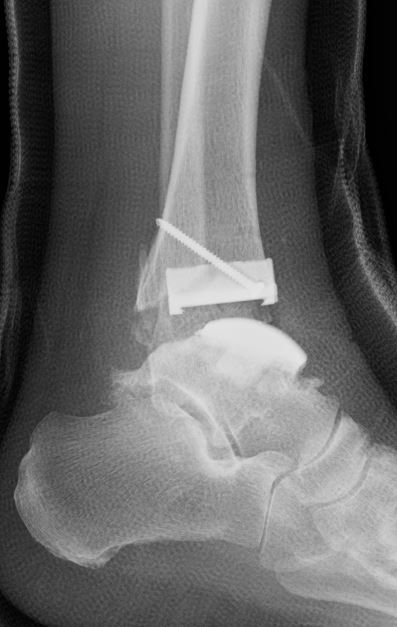

断層撮影は整形の領域でも行います。通常のX線撮影では骨や軟部組織が重なり合って見えにくいことがありますが、断層撮影では、特定の層(断面)だけをクリアに映し出すことができるため、骨や関節のより詳細な評価が可能です。特に、骨折、関節の変形、骨の異常などの診断において有効です。また、立位で検査を行うことも可能です。立位での撮影により、体重が関節や骨に与える影響を観察することができます。

通常のX線画像 |

断層撮影画像 |